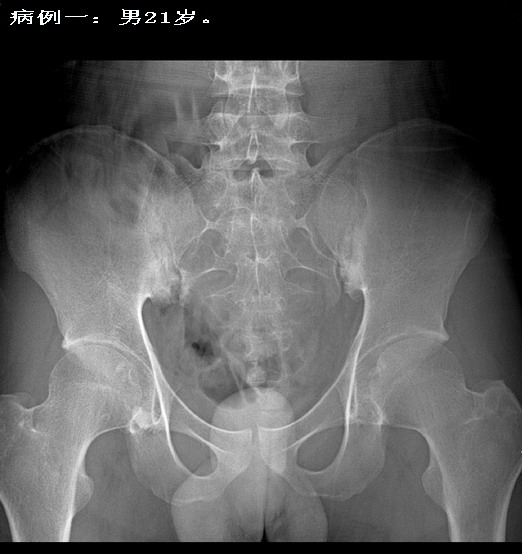

病例一:强直性脊椎炎早期病例.

男性患者,21岁,轻微腰背痛.双侧骶髂关节下缘破坏,腰椎曲度变直,骨质疏松,腰2-5椎体为方形,但尚未出现典型的竹节样改变。在北京阜外医院全面检查,诊断为强直性脊椎炎.

第一例是经过确诊的,注意一下双侧髋关节间隙一致性变窄,这也是强直性髋关节炎的表现.